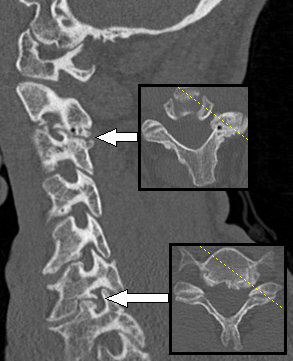

التصوير المقطعي المحوسب لرجل يعاني من اعتلال الجذور في العصب الفقري العنقي السابع الأيسر . يظهر داء الفقار مع نبتات عظمية بين الأجسام الفقرية C6 و C7 على الجانب الأيسر ، مما يتسبب في تضيق ثقبي في هذا المستوى (السهم السفلي ، يظهر أيضًا المستوى المحوري ) ، موضحًا الأعراض. يوجد أيضًا داء الفقار في المفصل الوجيه بين C2 و C3 ، مع بعض التضيق الثقبي في هذا المستوى (السهم العلوي) ، والذي يبدو أنه بدون أعراض.